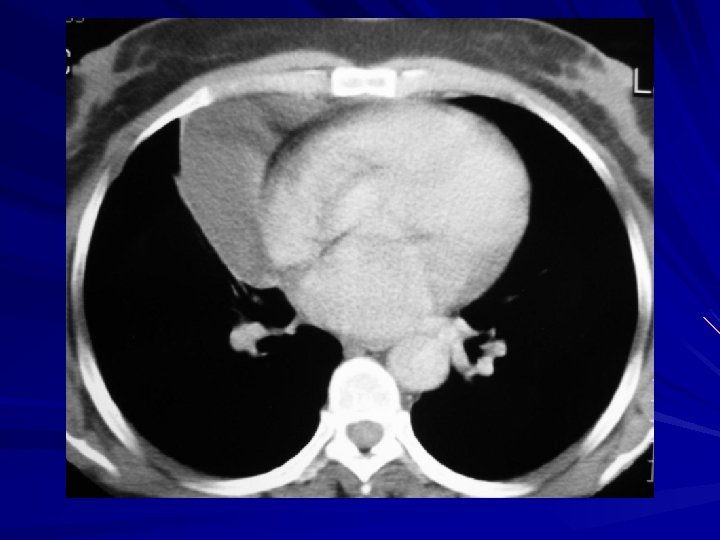

Plevral effüzyonda US Duyarlı: 5 -50 m. L sıvıyı bile saptayabilir Girişimsel işlemlere rehberlik yapabilir – Torasentez – Drenaj – Biyopsi Sıvının eksuda olduğunu anlayabilir – Ekojenik yapılar, septumlar

Plevral efüzyonda BT Çok duyarlı: minimal effüzyonlar saptanır Loküle effüzyonların saptanması Effüzyon – konsolidasyon ayrımı Ampiyem – apse ayrımı Nedeni ortaya koyabilir (pnömoni, malignansi, kalp yetmezliği, …) Benign – malign plevral hastalık ayrımı – %70 -80 doğruluk